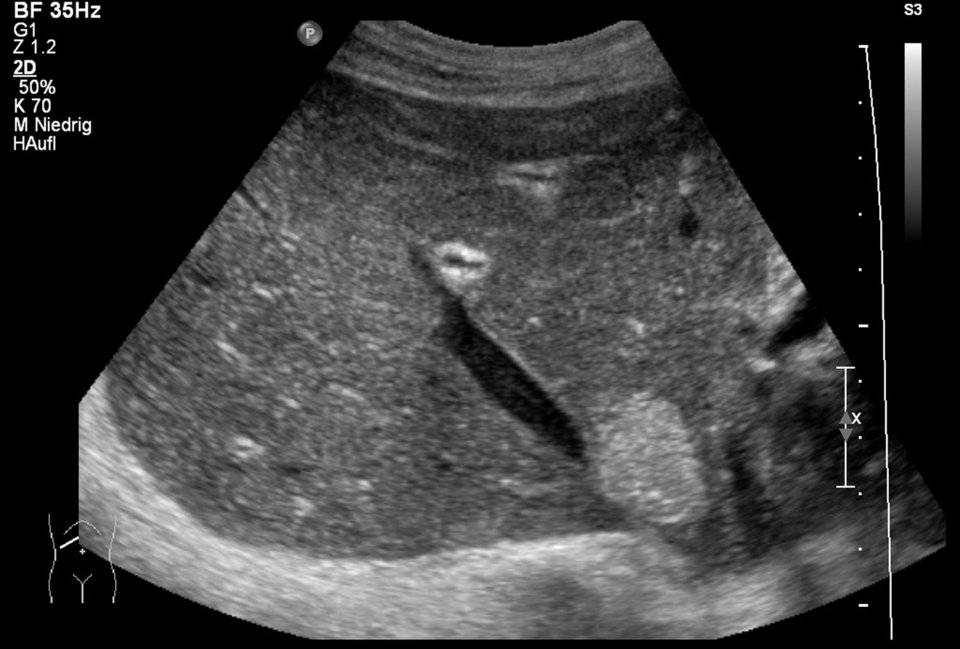

Bei diesem scharf abgegrenzten, echoreichen Herd handelt es sich um ein Hämangiom. Zudem sind Verkalkungen zu sehen. Bei diesem scharf abgegrenzten, echoreichen Herd handelt es sich um ein Hämangiom. Zudem sind Verkalkungen zu sehen. © Albertinen-Krankenhaus Hamburg/sonographiebilder.de

Der häufigste primäre Leber­tumor, das Hämangiom, findet sich bei bis zu 20 % der Bevölkerung. Mehr als 70 % dieser Läsionen lassen sich mit B-Bild-Sonographie bzw. Farbdoppler erkennen (scharf abgegrenzte echoreiche Herde). Wenn nicht, helfen kontrastverstärkte Verfahren (CEUS oder MRT).